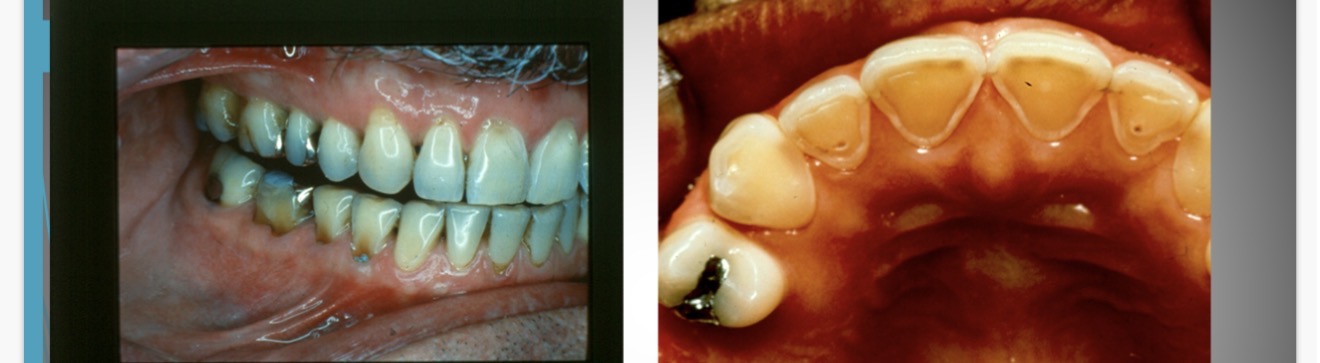

Amelogenesis imperfecta

-Hereditary disorder

-Enamel is very friable and may flake away.

-Scaling procedures should be modified